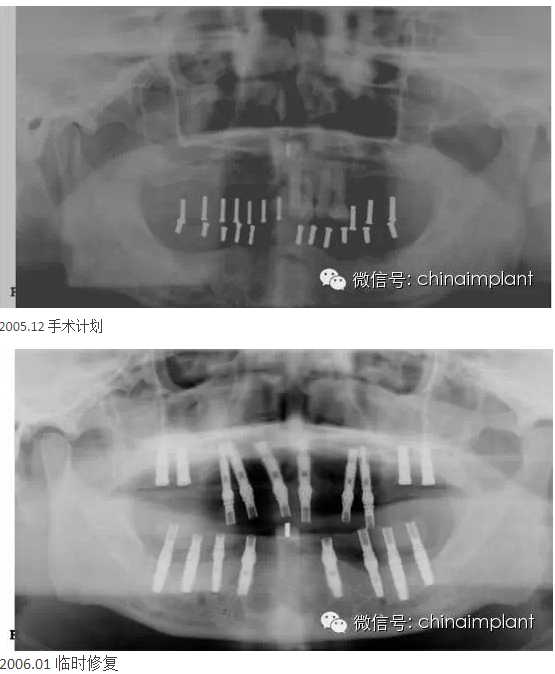

本案例已經(jīng)將近10年了(2005年12月),但是修復(fù)效果個(gè)人認(rèn)為很不錯(cuò),所以拿出來(lái)和大家分享。

從修復(fù)全景片上看到牙齒排列非常好